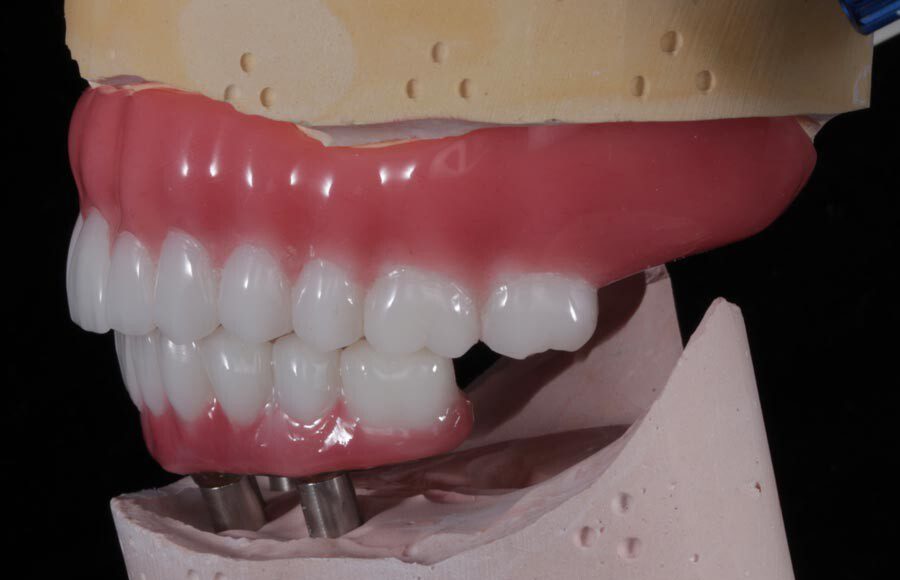

Smile GalleryImplant RestorationsImplant Dentures Post-op smiling 1 of 32 Pre-op close up smiling Pre-op lips retracted smiling Pre-op panoramic x-ray Implants in upper jaw (occlusal view) Implants in lower jaw (occlusal view) Panoramic x-ray of implants First set of try-ins – upper denture First set of try-ins – lower fixed provisional Delivered try-ins (lips retracted) Close adaptation to gums and appropriate emergence profile of lower fixed provisional Gum tissues have been molded by a convex provisional Delivered try-ins Second set of try-ins (lips retracted) Close adaptation to gums and appropriate emergence profile of second set of lower fixed provisional Delivered second try-ins Definitive restorations on casts (frontal view) Definitive restorations on cast (right side) Definitive restorations on cast (left side) Definitive upper overdenture (occlusal view) Definitive lower fixed titanium-acrylic hybrid restoration (occlusal view) Definitive lower fixed titanium-acrylic hybrid restoration (frontal view) Definitive lower fixed titanium-acrylic hybrid restoration (tissue side view) Healthy molded gum tissues on lower prior to delivery of lower fixed hybrid restoration Healthy gum tissues on upper prior to delivery of upper overdenture Definitive restorations (frontal, lips retracted) Definitive lower restoration (frontal) Definitive restorations (right side) Definitive restorations (left side) Definitive lower restoration (occlusal view) Definitive upper restoration (occlusal view) Post-op panoramic x-ray Post-op smiling